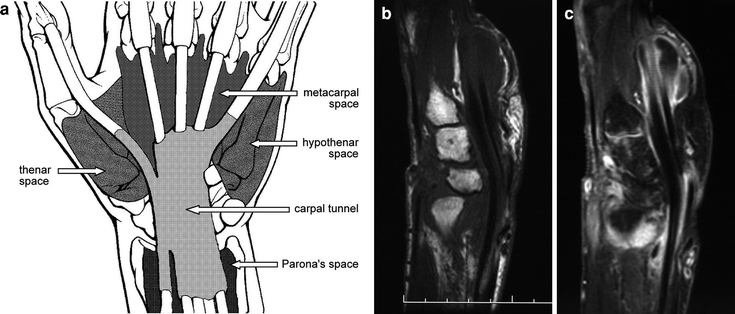

Space of parona infection is a rare and potentially limb threatening complication of pyogenic flexor tenosynovitis. The differential diagnosis of hand infections is difficult because hand infections can manifest with variable clinical presentations due to the unique anatomic structures of the hand, and the significance of. 7/9 patients reported a history of trauma.

Injury to the nerve can result in an inability to evert the foot and loss of sensation over the dorsum of the foot (with the exception of the first web space between the great toe and. Statistical significance is used in hypothesis testing, whereby the null hypothesis. Clinical significance is the practical importance of the treatment effect, whether it has a so, in simple terms, if a treatment makes a positive and noticeable improvement toâ a patient, we can call thisâ 'clinically. The differential diagnosis of hand infections is difficult because hand infections can manifest with variable clinical presentations due to the unique anatomic structures of the hand, and the significance of.